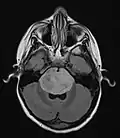

Anatomy

- Brainstem Glioma